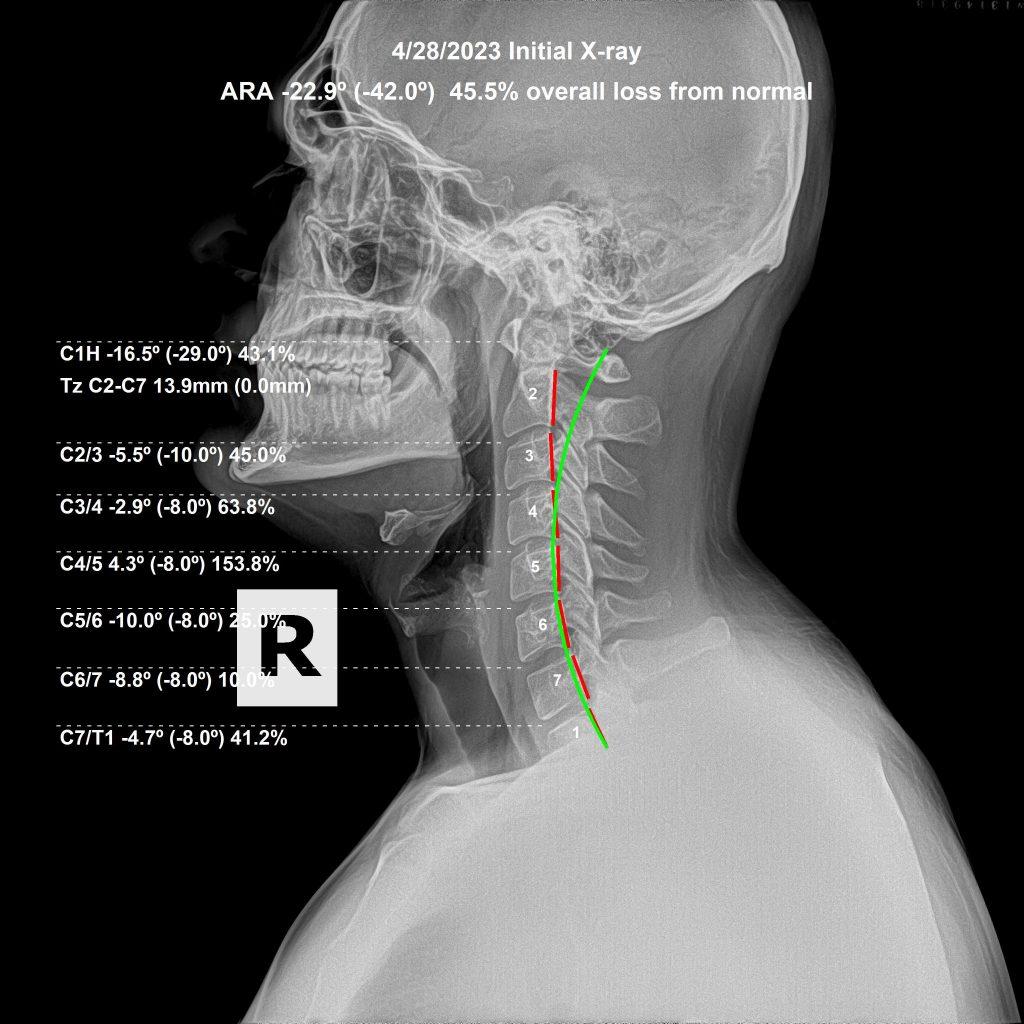

Lateral cervical X-ray before chiropractic correction

Lateral View — Initial

A 27-year-old male suffered a gym injury to his neck, presenting with headaches, double vision from a newly developed lazy left eye, facial pain and paresthesias, and paresthesias radiating into his arms. After 3 months of care, all symptoms had resolved — including the lazy eye. He was even showing signs of holding his adjustments.